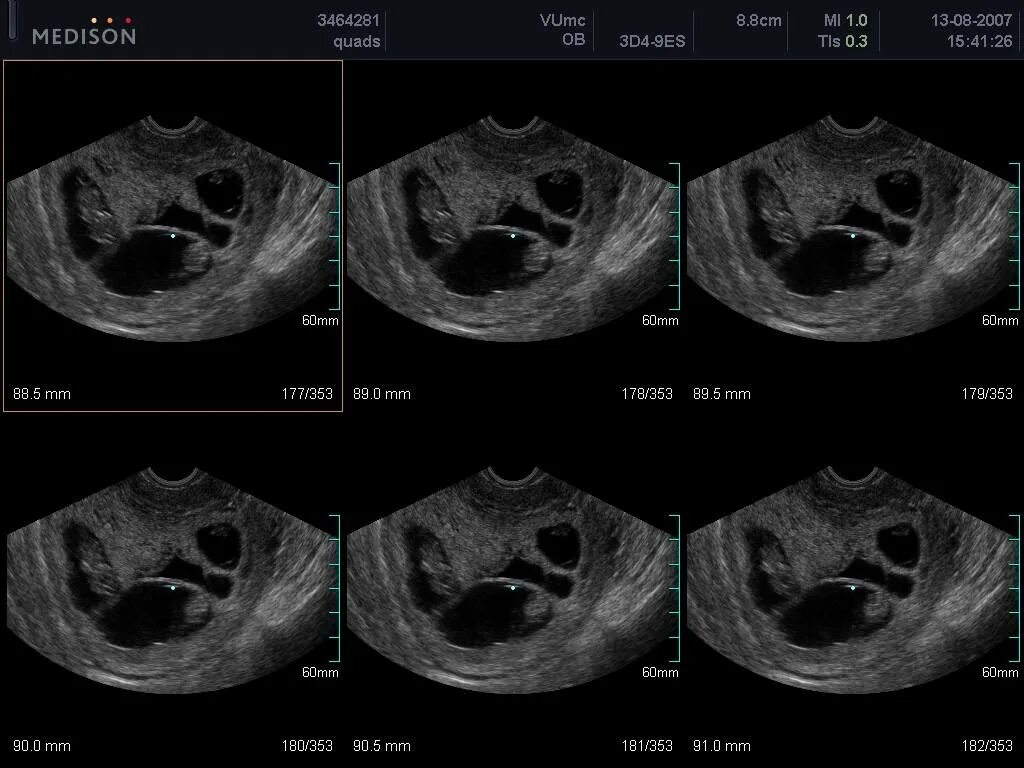

На узи можно определить раннюю беременность